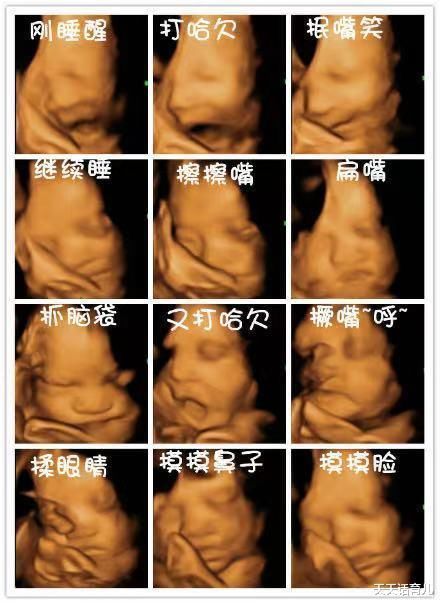

留下珍贵孕期纪念

四维彩超可对胎儿特定体表进行清晰检查,可将检查的整个过程刻录成光盘,将宝宝在宫内的特定部位的动作记录下来,如吐舌头、微笑、皱眉头、肢体动作等,是独一无二的孕期纪念,也是送给未来宝宝的珍贵礼物。